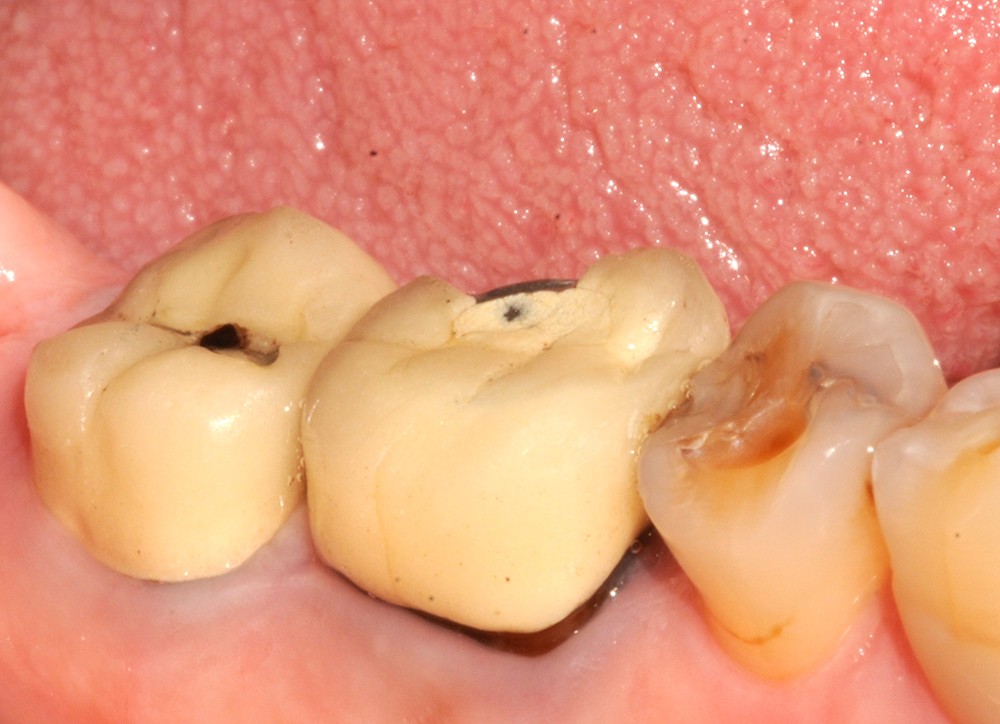

Aspect clinique et radiographique des lésions d’abrasion

Cliniquement, les lésions d’abrasion sont caractérisées par des facettes lisses, une absence de convexité et des bords à angles vifs. La flexibilité du ligament alvéolo-dentaire va entrainer un frottement au niveau des points de contact, qui peuvent se transformer en surfaces de contact (fig. 2c-d, 3 et 4b-c).